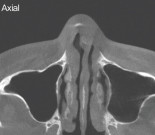

얼굴의 균형을 바꾸는 수술, 코에도 영향 현대 사회에서 양악수술은 단순한 교정 목적을 넘어  얼굴의 균형과 인상을 변화시키는 미용적 수술로 자리 잡았다. 특히 돌출입이나 얼굴 비대칭 등 외형적인 문 제를 개선하기 위해 수술을 선택하는 환자들이 꾸준히 늘어나고 있다. 그러나 얼굴의 중심부를 이루는 상·하 악 구조를 이동시키는 과정에서 코와 비중격에도 영향 을 미칠 수 있다는 점은 상대적으로 간과되기 쉽다. 실제로 양악수술 후 코 모양의 변화나 비호흡 장애를 호 소하는 환자들이 점차 증가하고 있으며,수술 후 코의 기능적·미용적 재건에 대한 중요성이 부각되고 있다. 양악수술은 상악과 하악을 얼굴뼈로부터 분리해 전진 이나 후진시켜 부정교합을 교정하는 수술이다. 미용 성형에서는 주로 돌출입을 교정하기 위해 상악을 후진 시키는 수술을 일반적으로 지칭한다. 이러한 상악뼈 수술의 경우 양쪽 광대뼈의 아래쪽뿐만 아니라 비중격 바닥 부분도 얼굴뼈에서 분리되어야 하기에 수술 후 비 중격 만곡이나 붕괴의 원인이 되며 이는 코끝의 퍼짐, 코막힘의 원인이 되기도 한다.이번 호에서는 상악수술 후 코의 기능적·미용적 변형 을 비중격 재건과 코 성형으로 수술한 예를 리뷰하고자 한다케이스 소개1997년생 남자 환자가 지속적인 코막힘과 콧물을 증상으로 내원하였다. 양악수술과 코 필러 및 실 삽입 수술이력이 있었다. 수술 전 이학검사상 좌측에서 우측으로 의 역C형 사비가 보였으며 비주와 비공의 비대가 관찰되 었다 수술 전 사진. 역C형 사비와 흡기 시 우측 비익연골의 허탈이 확인되었다.비주와 비공의 비대칭도 보였다수술 전 CT. 비중격 만곡이 보였다. 골부와 연골부의 좌측 만곡과 spur가 관찰되며 전체적으로 C-shape deviation이 확인되었다. 비중격 만곡으로 인해 측면에서 비중격의 음영 소실도 보였다.Cottle test에서는 좌측에서 positive가 관찰되 었으며, 흡기 시 우측 비익연골의 허탈이 관찰되었다. 내원 당시 시행한 CT상 비중격의 골부와 연골부 상단에서 좌측으로 만곡된 C-shape deviation이 확인되었다. 수술 전 CT. 비밸브 협착을 보였다. 비익연골의 내전과 비중격 미단 변형으로 인한 좌측 비밸브 협착이 확인되었다. 상악수술 후 삽입된 핀이 비골 바닥 부분에 산재되어 있다.  이러한 소견은 이전 양악수술에 의한 결과일 가능성이 있다. 또한 비익연골의 내전과 비중격 미단부의 변형으로 인한 좌측 비밸브 협착이 관찰되었다.수술 전 비내시경. 비중격이 전체적으로 좌측으로 만곡되어 C-shape deviation이 확인되었다. 미단부 변형으로 인해 좌측 비밸브 협착이 보였다.비중격 만곡은 CT보다 내시경상에서 더 심하게 나타났다내시경 검사에서는 CT에서보다 더 심한 비중격 만곡이 관찰되었으며, 비밸브 협 착이 보여 비중격 및 비밸브 교정술, 하 비갑개 점막 절제술을 계획하였다. 비중격 및 비밸브 교정 전. 연골부 일부가 이전 양악수술로 인해 소실된 모습이다. 비중격이 전체적으로 좌측 만곡되어 C-shape deviation이 확인되었다.수술장 소견상 비중격 연골부 일부가 이전 양악수술로 인해 소실된 모습이 보였고, 전체적으로 좌측으로 만곡된 C-shape deviation이 확인되었다. 또 한 비익연골의 내전과 비중격 미단부의 변형으로 인해 좌측 비밸브 부위가 좁아져 있음이 관찰되었다.수술 중 채취 재료. 8th costal cartilage오른쪽 8th costal cartilage를 채취한 후, 좌측으로 휘어 있는 미단부 연골 부위를 nasal spine 우측으로 이동시켜 고정함으로써 비중격의 휨을 전체적으로 우 측으로 이동시켜 bone–cartilage의 휨을 일치시켰다.  좌측으로 휘어 있는 연골 부위를 nasal spine 우측으로 이동시킨 후 고정하여 비중격의 휨을 전체적으로 우측으로 이동시켜 bone-cartilage의 휨을 일치시켰다. 채취한 costal cartilage를 이용해 우측 비중격의 상단부터 미단까지 넓게 batten graft를 시행하여 전체적인 만곡을 교정하였으며, 남은 만곡을 교정하기 위해 우측 비중격 상·하단에 각각 batten-spreader graft를 시행하였다.채취한 costal cartilage를 이용해 우측 비중격의 상단부터 미단까지 넓게 batten graft를 시행하여 전체 적인 만곡을 교정하였고, 남은 만곡을 추가로 교정하 기 위해 우측 비중격 상·하단에 각각 batten spreader graft를 시행하였다. 이후 고주파를 이용하 여 양측 하비갑개 점막에 coblation을 시행하였다. 양악수술 이후 코의 구조적 약화와 그 대응콧등 융기 목적으로 제작된 실리콘, 거푸집, 연골 입자 몰딩비중격 재건 후 자가늑연골을 이용하여 비중격연장술 을 시행하였다. 또한 콧등의 이물질(실)을 제거함과 동 시에, 실리콘 형태의 거푸집을 이용해 연골 입자를 몰 딩한 후 코에 이식하였다. 이러한 접근을 택한 이유는 양악수술 이후 실리콘을 사용할 경우 염증 발생 위험 이 높고, 염증이 발생하면 비중격 손상이 빠르게 진행 되기 때문이다. 따라서 이와 같은 경우에는 철저히 무보형물 방식으로 수술하는 것이 유리하다. 수술 후 사진. 사비 및 코끝 처짐과 콧대 불규칙 등이 개선되었다.양악수술 후 코 성형에서는 비중격의 약화나 붕괴가 흔하게 발생하며, 이물질인 핀이 비골 바닥에 삽입되어 있는 경우도 많다. 이로 인해 코끝의 융기가 매우 어렵고, 비중격 염증에 기인한 코의 염증 빈도가 높아 예후 도 좋지 않다. 따라서 양악수술 이후의 코 성형은 기능 적 측면에서 비중격 재건이 반드시 동반되어야 하며, 코 성형 시에는 무보형물 방식이 가장 바람직하다